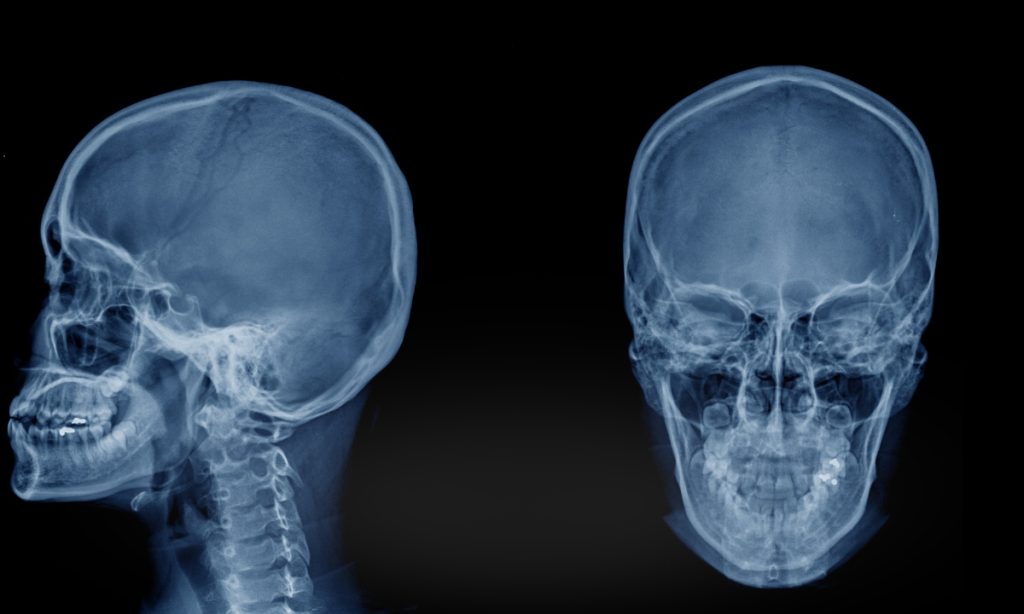

A articulação temporomandibular é uma das estruturas mais complexas e funcionalmente exigidas do corpo humano. Localizada entre o osso temporal do crânio e a mandíbula, essa articulação desempenha um papel essencial em funções cotidianas como falar, mastigar, engolir e realizar movimentos faciais. Sempre que abrimos ou fechamos a boca, essa articulação entra em ação de […]

A disfunção da ATM, também conhecida como DTM (disfunção temporomandibular), é uma condição que pode provocar diversos sintomas na região da mandíbula e da face. Muitas pessoas convivem com sinais como dor na mandíbula, estalos ao abrir a boca, dificuldade para mastigar ou dores de cabeça frequentes sem saber que esses sintomas podem estar relacionados […]

Se você já sentiu dores na mandíbula, estalos ao abrir a boca ou dificuldade para mastigar, é provável que tenha se perguntado O Que É ATM? e como isso pode afetar sua saúde bucal e qualidade de vida. Compreender o que significa ATM é o primeiro passo para buscar o tratamento adequado e aliviar esses […]